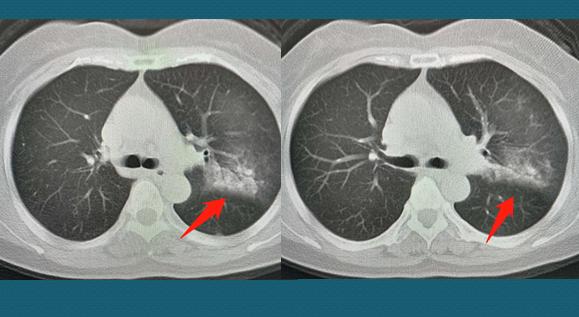

这位女士以前就有慢性咳嗽的毛病,春节前的新闻接触多了有点慌,呼吸科医生听诊左肺确实有问题,就让她戴好口罩,过来做了肺部CT:

左肺见到斑片状和淡片状密度增高影,边界不清,里面可以看到充气支气管影,肺门及纵隔无淋巴结肿大,符合炎症的特点。

病人很慌,医生很稳,因为从CT影像上不具备病毒性肺炎的特点,化验结果显示病人血象升高,支持一般性的细菌感染。最重要的是,病人近期没有接触史,病毒检测也没有阳性发现,输输液就能好。

虽然医生这么安抚,病人心里还是七上八下,好在输液一次之后咳嗽症状就好转了。7天后回来复查CT,大部分吸收了: